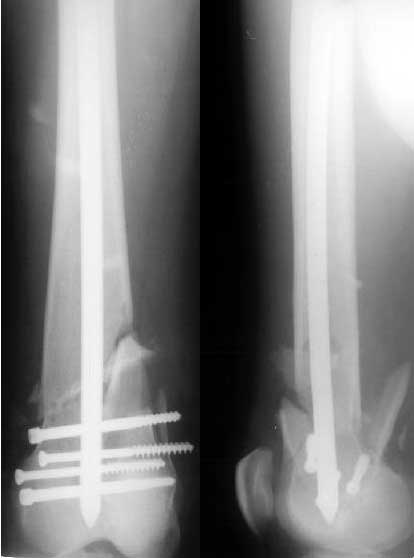

Пациент 27 лет оперирован 2.04.02 через 2 недели после открытого перелома дистального отдела бедренной кости (1 снимок).

Сделан антеградный закрытый интрамедуллярный остеосинтез UFN 11 мм (2 снимок). Вторая нога была ампутирована по месту первичного поступления. Для возможности ранней нагрузки использованы блокирующие винты 6 мм, для чего дистальные отверстия были рассверлены. К двум месяцам начал вставать на костыли, до того занимался разработкой движений в колене. Эти циклические движения в сочетании с тем, что зона концентрации нагрузок приходилась как раз на уровень отверстия, и что перелом открытый и тяжелый и не успел прочно схватиться, привели к перелому стержня 8 июня (3 снимок). Вчера госпитализировали. Такое осложнение у нас впервые. Пока думаем про реостесинтез - вытолкнуть дистальный отломок через дистально, да и через то же отверстие заштифтовать ретроградно. Илиналожить аппарат после удаления центрального отломка стержня, если что-то не будет получаться. Или подумать про пластинку?Заранее спасибо.